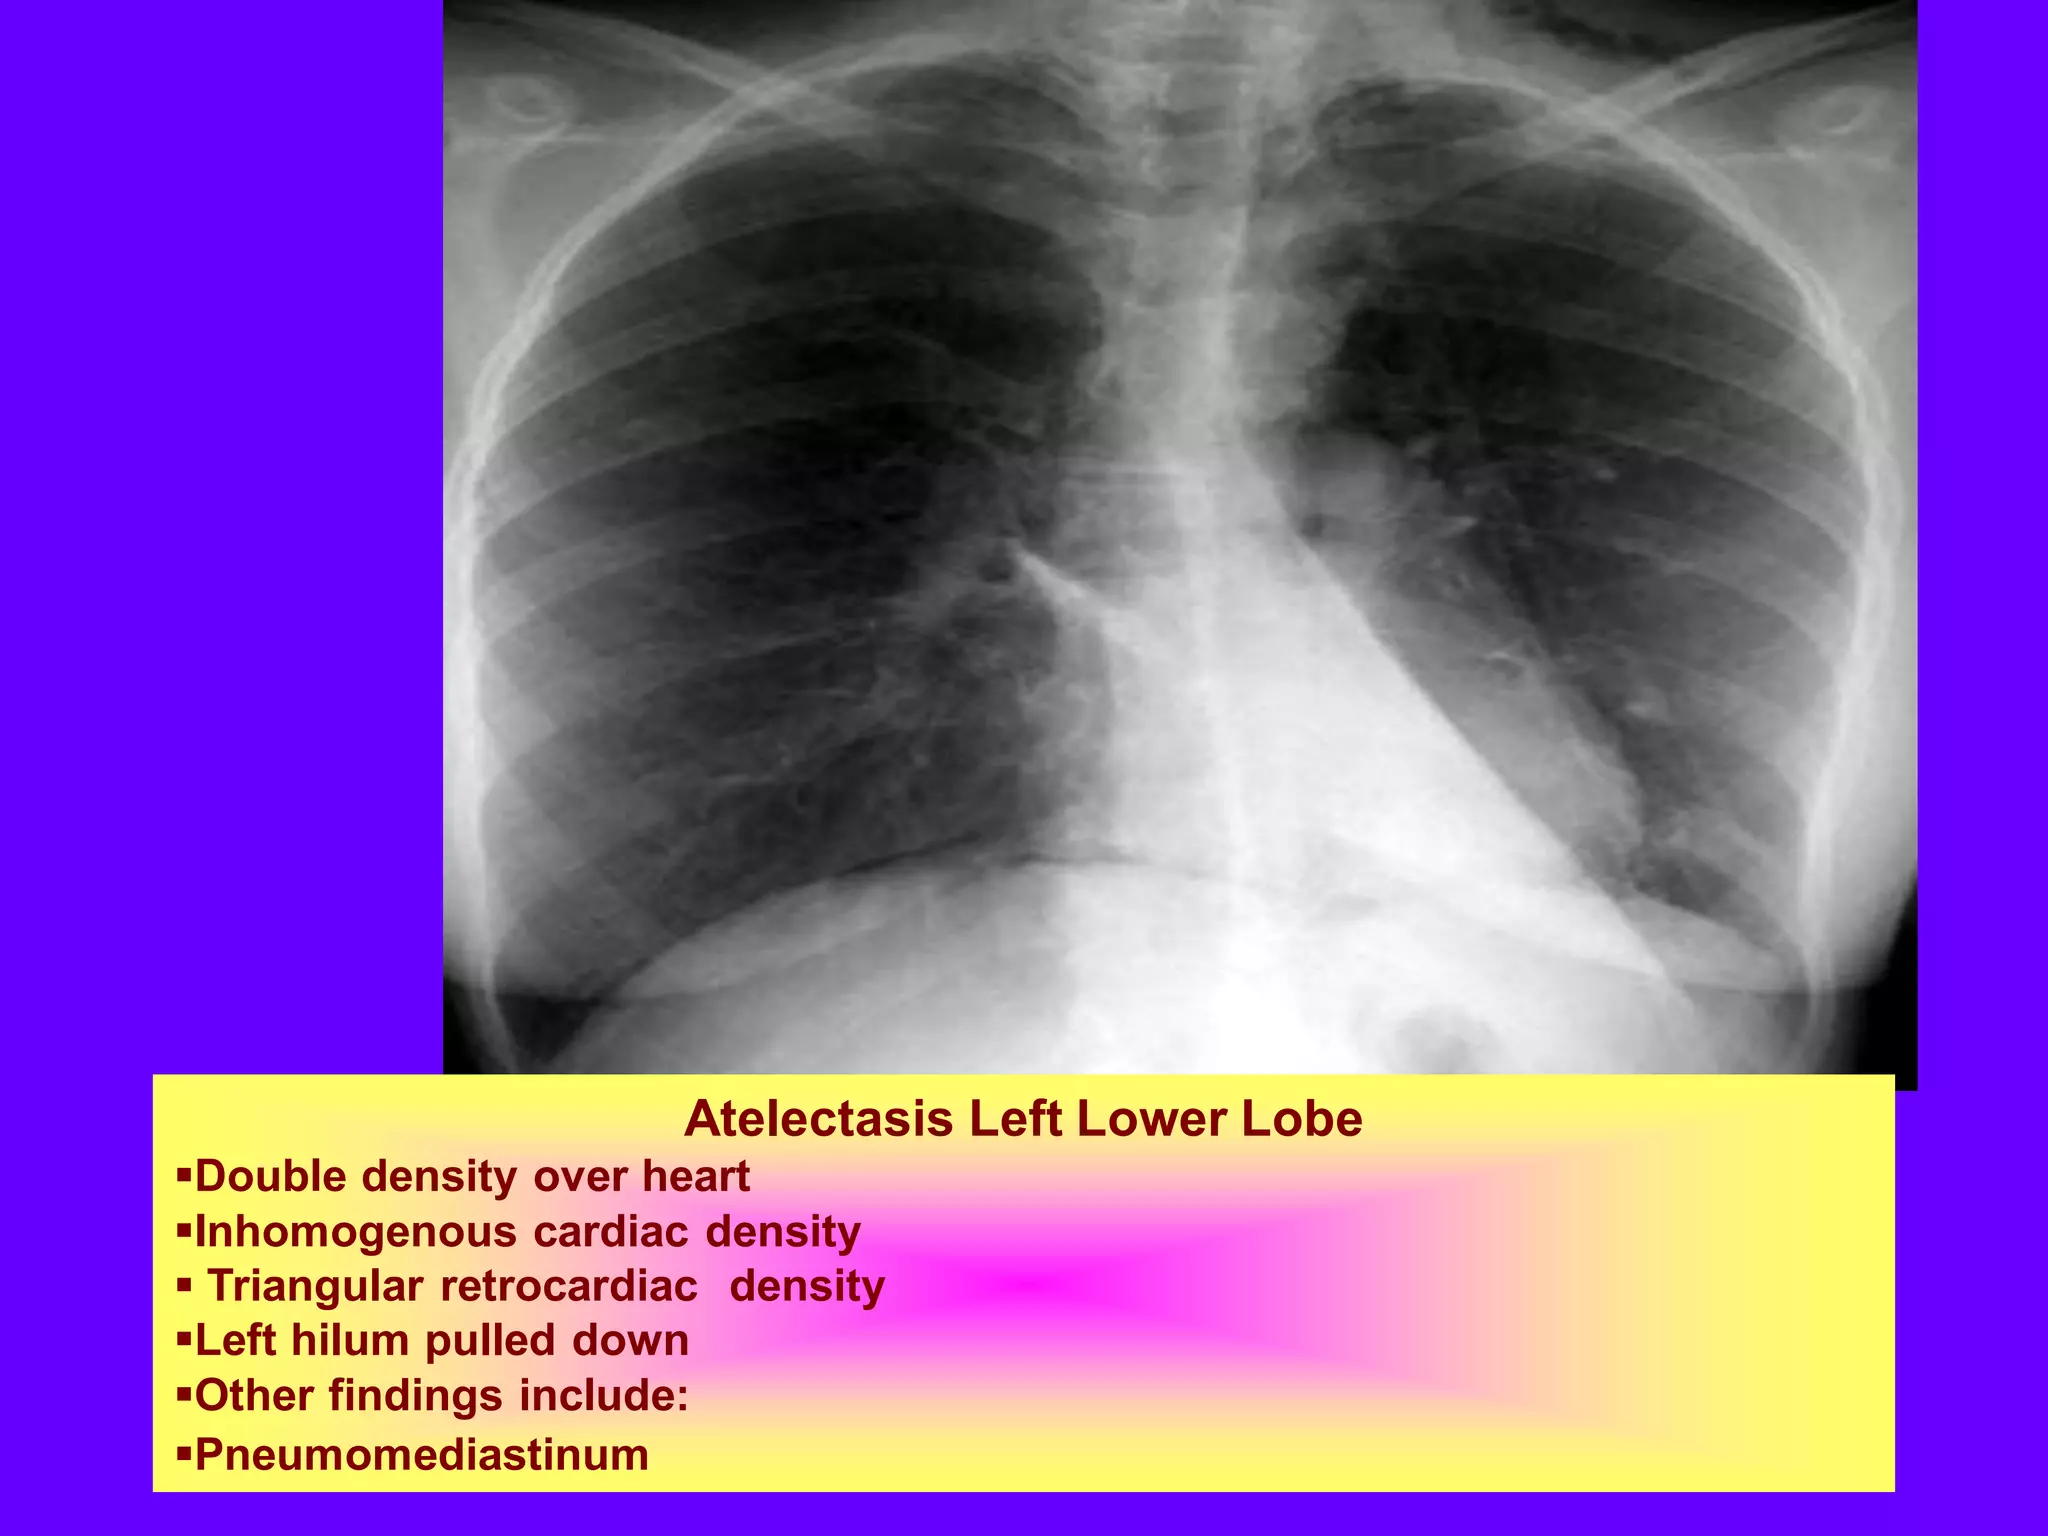

Atelectasis Left Lower Lobe

Double density over heart

Inhomogenous cardiac density

 Triangular retrocardiac density

Left hilum pulled down

Other findings include:

Pneumomediastinum